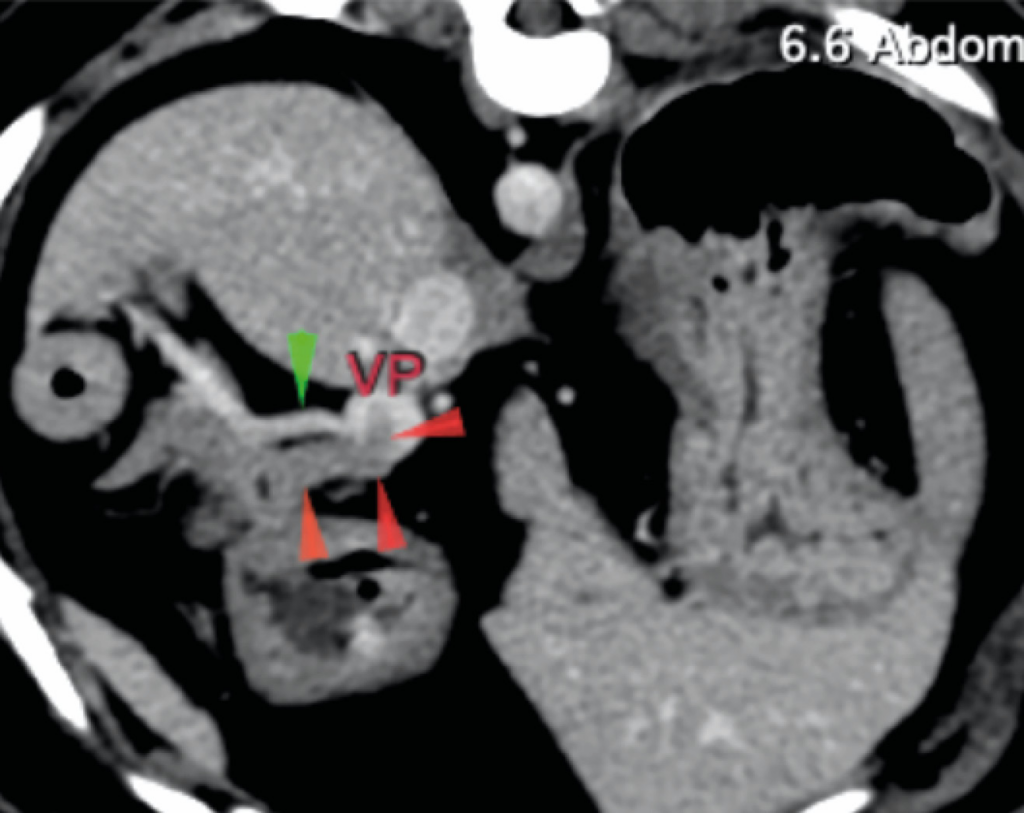

La ecografía abdominal reveló una lesión en el parénquima del cuerpo pancreático con posible invasión vascular a la vena porta. Una TC abdominal con contraste evidenció la lesión asociada al cuerpo del páncreas, con invasión de la vena porta (imágenes 1A y 1B), junto con la presencia incidental de un cuerpo extraño gástrico y signos de enfermedad degenerativa torácica y lumbosacra. Se realizó la extracción endoscópica del cuerpo extraño mediante gastroscopia durante el procedimiento anestésico.

Se realizó una laparotomía exploratoria por línea media ventral y se observó un nódulo en el cuerpo del páncreas con invasión de un trombo tumoral en la vena porta y otro nódulo de menor tamaño en el lóbulo izquierdo (imágenes 2A y 2B).